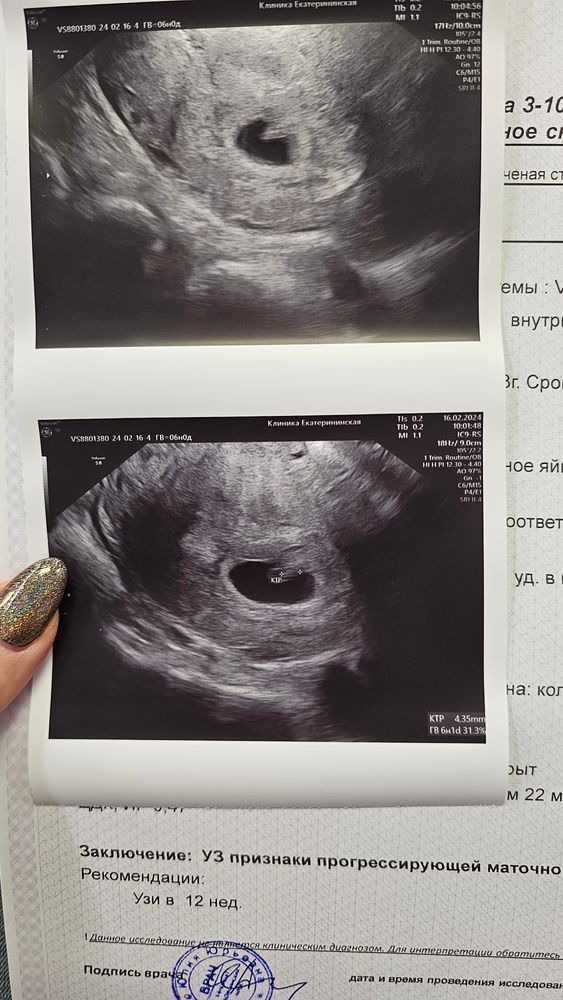

Узи 6 недель

Просто Катя, у меня было 4 зб Все на сроке 6-10 недель Хочется дожить до скрининга не на панике 😅